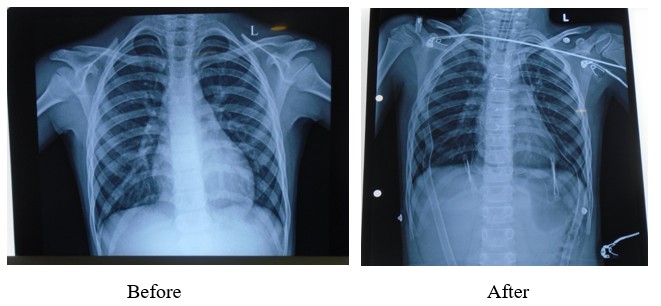

X-Ray

Procedure Images